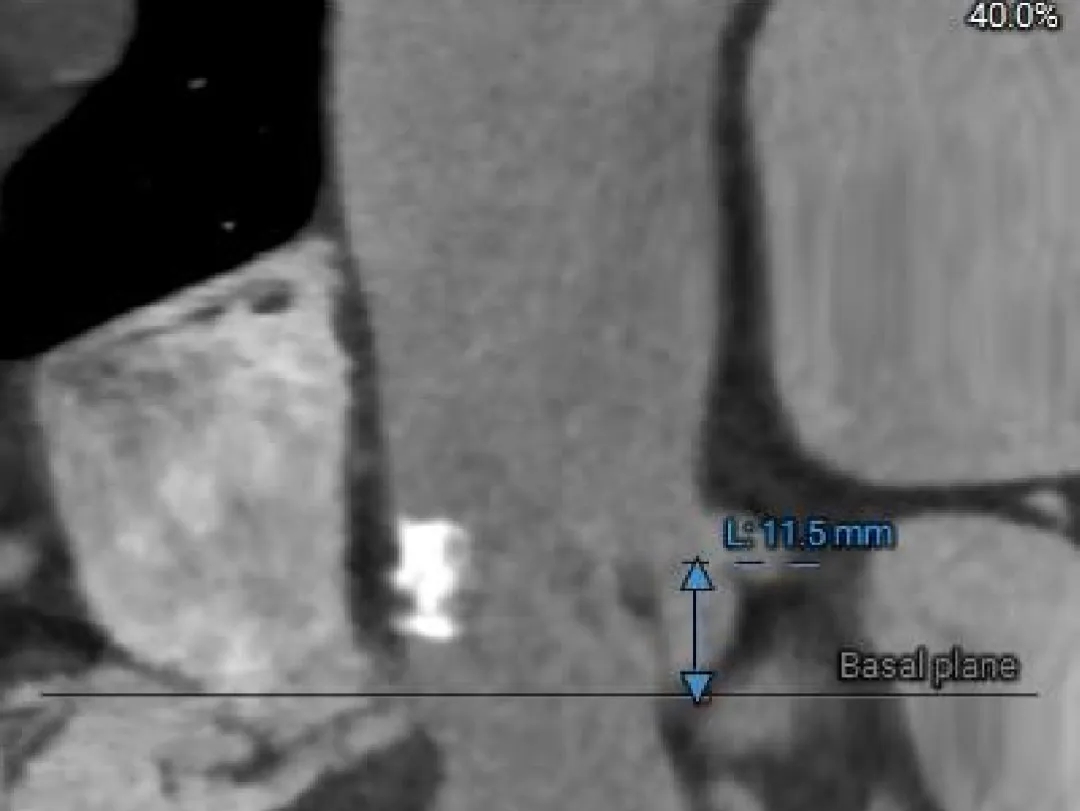

主动脉根部测量

Left Coronary

11.5mm

LCA & Leaflet

12.2mm<13.0mm

Right Coronary

10.5mm

RCA & Leaflet

13.3mm<13.5mm

-

左、右冠脉高度偏低

双侧瓣叶偏长

结合SOV、STJ内径评估冠脉风险适中,结合球扩情况充分评估